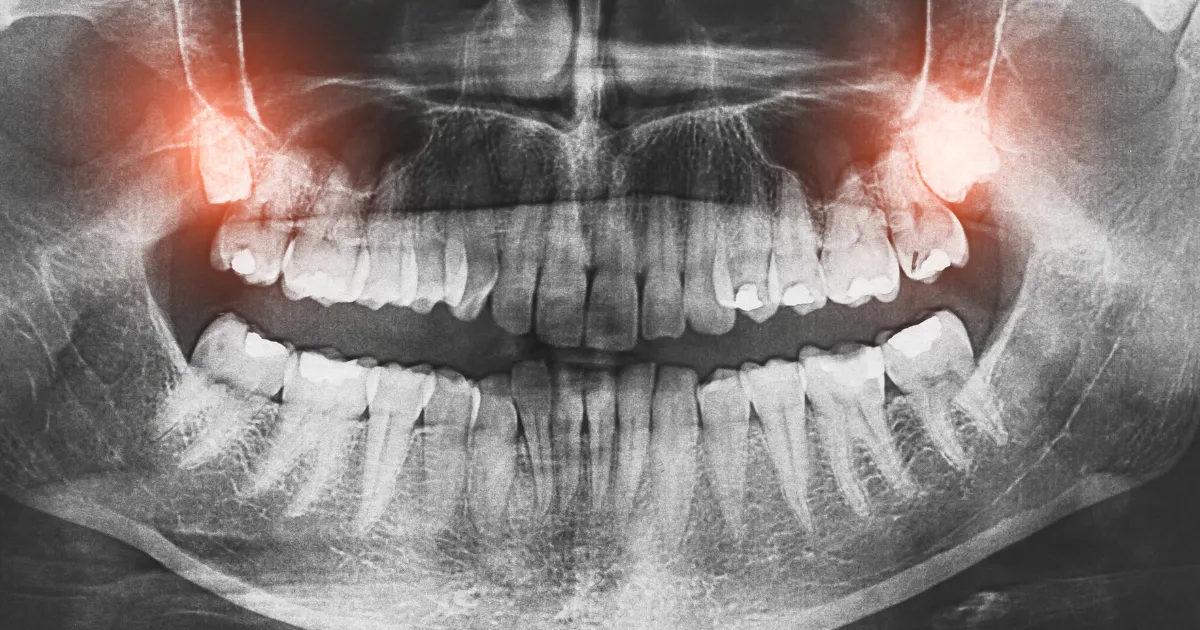

そもそも親知らずとは?

親知らずは、個人差がだいぶありますが20代前後で生えてくる一番奥の歯(前から数えて8番目の歯、第三大臼歯)を指してます。

親知らずは生え方に個人差があり、まっすぐに生えることもあれば、傾いたり歯肉に埋まったままの場合もあります。

親知らずが直接的や関節的な原因となって歯並びが乱れたり、痛みや炎症を引き起こしたりすることが多く、歯列矯正や他の歯に影響を与える場合には抜歯をドクターが検討します。